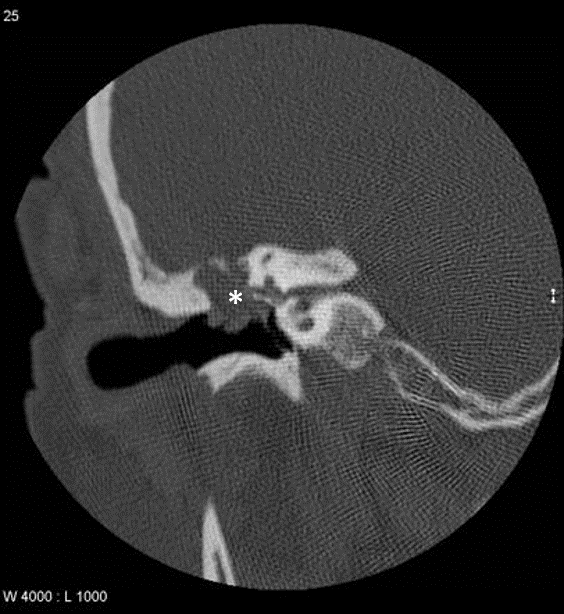

Un test d’audition (audiogramme et tympanogramme) et un scanner de l’os temporal (os de l’oreille) sont nécessaires pour le diagnostic et la planification du traitement.